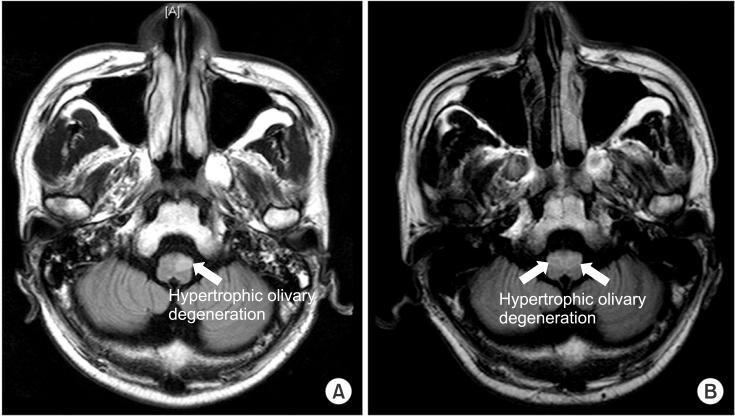

A pontine intracranial hemorrhage (ICH) evokes several neurological symptoms, due to the various nuclei and nerve fibers; however, hearing loss from a pontine ICH is rare. We have experienced a non-traumatic pontine ICH patient, with hearing loss. A 43-year-old male patient had a massive pontine hemorrhage; his brain magnetic resonance imaging revealed the hemorrhage on the bilateral dorsal pons, with the involvement of the trapezoid body. Also, profound hearing loss on the pure-tone audiogram and abnormal brainstem auditory evoked potential were noticed. Fifty-two months of long-term follow-up did not reveal any definite improvement on the patient's hearing ability.

桥脑出血(ICH)由于各种神经核团和神经纤维会引发多种神经症状;然而,桥脑出血导致的听力丧失较为罕见。我们遇到过一名非创伤性桥脑出血患者伴有听力丧失。一名43岁男性患者发生了大量桥脑出血;他的脑部磁共振成像显示双侧脑桥背侧出血,累及梯形体。此外,纯音听力图显示重度听力丧失,脑干听觉诱发电位异常。52个月的长期随访未发现该患者听力能力有任何明显改善。